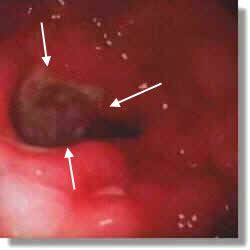

The arrows point to an ulcer in the lining of the stomach.